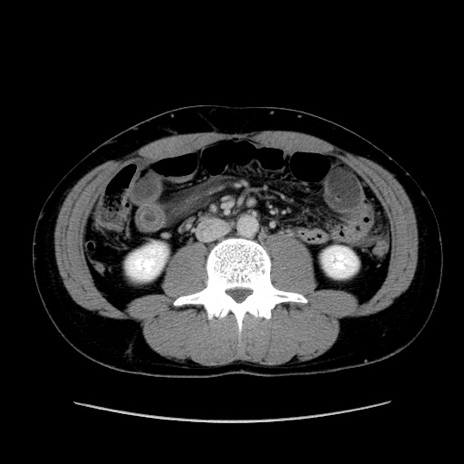

症例36(横断像)

【症例】20歳代 男性

【主訴】心窩部痛

【現病歴】今朝より上腹部痛あり。一旦軽快していたが再度出現したため救急要請。昨日夕に白身の魚を含む刺身を食べた。

【身体所見】BP 136/89mmHg、HR 74/min、BT 37.0℃、腹部:膨満、軟、心窩部に圧痛あり。反跳痛なし、筋性防御なし、腸雑音やや亢進あり。

【データ】WBC 17700、CRP 0.48